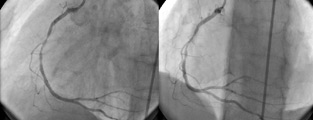

Comparación entre angiotc coronario y angiografía convencional en patologia ateroesclerótica coronaria

Demostrar la viabilidad para el estudio de patología cardíaca coronaria […]